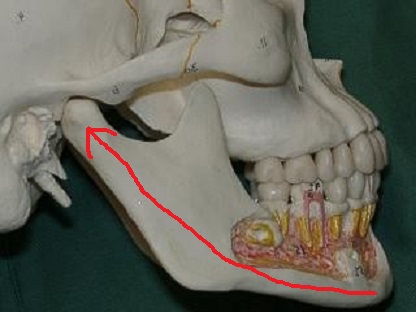

介達骨折=力が加わった場所から離れた場所に起きた骨折を介達骨折(かいだつこっせつ)といいます。

オトガイ部に加わった力が下顎頭にダメージを与えます。